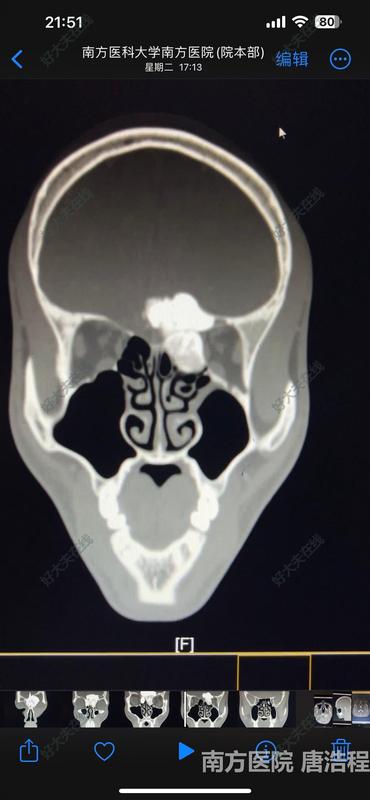

患者因“头痛伴有鼻部、眼部畸形”就诊,行鼻窦CT检查发现鼻窦前颅底眼眶巨大骨瘤,肿瘤占据双侧额窦、筛窦,突入颅内和左侧眼眶